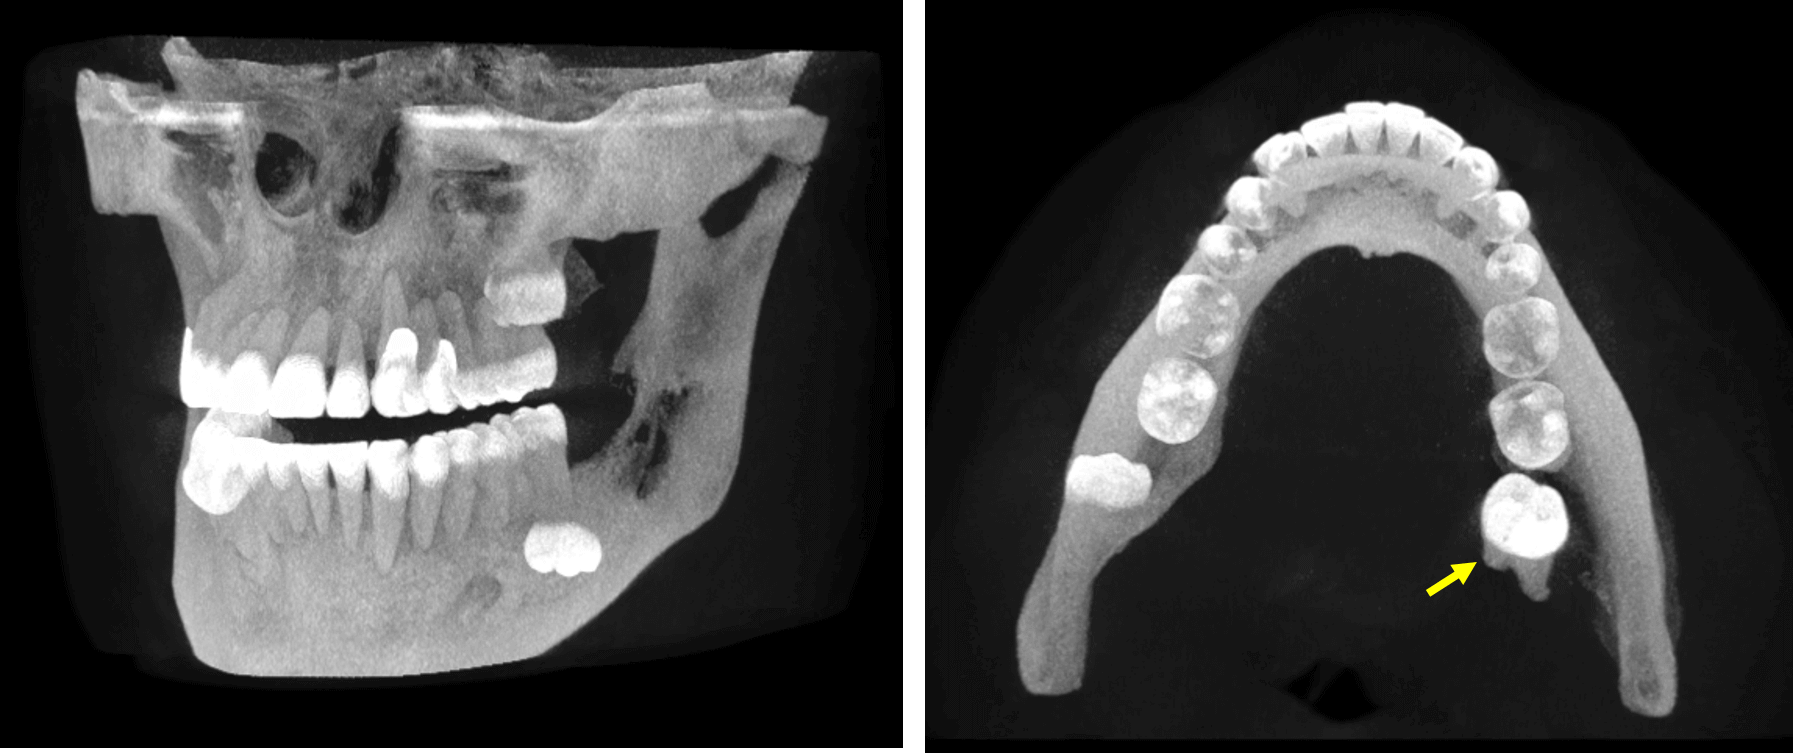

En la evaluación con tomografía computarizada cone beam, se realizó la reconstrucción panorámica del maxilar inferior (Fig.1) en la cual se observa el órgano dentario 38 en aparente posición mesioangular e invertida con la corona en relación con el reborde basal mandibular, asi como una lesion osteolítica la cual compromete las raíces de este tercer molar, extendiéndose de forma superior hasta el reborde alveolar y comprometiendo el tercio inferior de la rama ascendente. Asi mismo, se observa la impactación del órgano dentario 48, en posición mesioangular y con la corona en relación con una imagen hipodensa a nivel pericoronario. Además, se observa el acortamiento de la longitud radicular en las raíces de los órganos dentarios 46 y 47.

En la evaluación con tomografía computarizada cone beam, se realizó la reconstrucción panorámica del maxilar inferior (Fig.1) en la cual se observa el órgano dentario 38 en aparente posición mesioangular e invertida con la corona en relación con el reborde basal mandibular, asi como una lesion osteolítica la cual compromete las raíces de este tercer molar, extendiéndose de forma superior hasta el reborde alveolar y comprometiendo el tercio inferior de la rama ascendente. Asi mismo, se observa la impactación del órgano dentario 48, en posición mesioangular y con la corona en relación con una imagen hipodensa a nivel pericoronario. Además, se observa el acortamiento de la longitud radicular en las raíces de los órganos dentarios 46 y 47.

En la representación tridimensional (Fig.5) se observa el desplazamiento lingual del órgano dentario 38, por fuera de la estructura mandibular y localizada en el interior del tejido blando por lingual, lo cual sugiere el desplazamiento del órgano dentario en relación con una secuela quirúrgica.